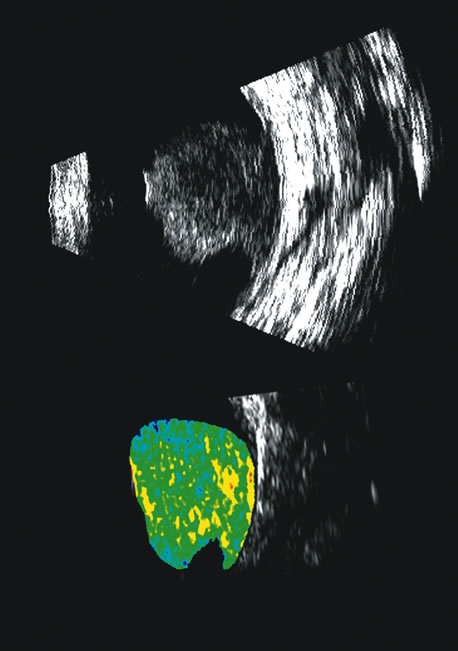

Fig. 25. A 3D reconstruction of serial scans of a posterior pole melanoma taken with a 10 MHz transducer (left) shows the extent and relative asymmetry of the tumor within the vitreous cavity. 3D biometry can be useful for treatment planning for radiotherapy and brachytherapy. 3D reconstructions of 50 MHz serial ultrasound scans and parameter images of a melanoma involving the ciliary body and anterior uvea (center, right) before and after treatment with combined ultrasound hyperthermia and brachytherapy. Changes in the concentration of ultrasound scattering elements related to tissue necrosis are seen as color scale in the pre- and postimage region of the tumor shifts, from blue, indicating relatively low acoustic concentration, to yellow and green, indicating higher concentrations of scatterers.

Spectral parameter imaging, a digital signal processing technique that examines the frequency content of backscattered ultrasound signals, has been shown to be predictive of increased lethality in certain patients and also to be useful in the in-vivo identification of high-risk melanomas for treatment staging.46–48 The shape, density, orientation, and number of scattering elements in a region influence not only the relative amplitude or brightness of a pixel on B-scan but the frequency content of the signal returned to the transducer.19 The concept of differentiating tissue backscatter in a quantitative manner rather than in simple qualitative descriptions of hypo-, iso-, and hyperechoic variations in gray scale allows for maximum use of information available in the digital ultrasonograms. These techniques can be extended to examining the functional anatomy of the eye as well as disease states other than solid tumors (Fig. 26).

Fig. 26. A gray-scale B-scan of a large collar-button melanoma (top) showing a relatively isoechoic button and base with some differences in internal speckle noted. The companion serial plane spectral parameter image (bottom) shows local differences in the size of ultrasound scatterers within the tumor, with size range increasing from blue to red.